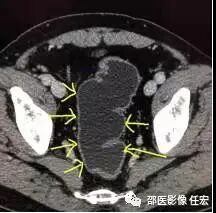

这时候再看图5,同一个患者同一个部位,检查前清洁灌肠后,向肛门注入清水,可见直肠被充盈起来了,壁很薄,一点都没有增厚。所以如果单单就图4,很容易被误诊为直肠癌。这也正体现了做CT之前胃肠道准备的重要性。如果临床配合不好,做的不足,会影像CT的诊断结果。

图6:这是图4患者的图像,向肛门注入清水,整个结肠充盈了清水后,壁薄,显示得一览无遗。